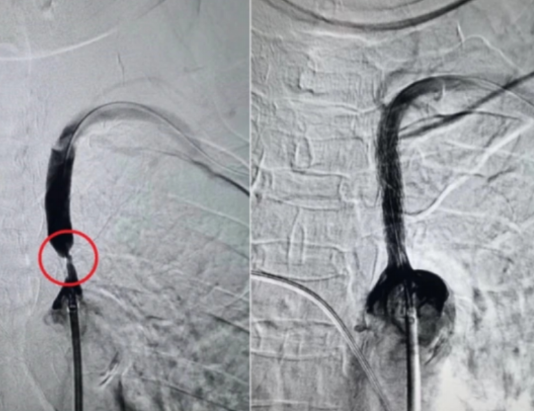

面对这个“偷血大盗”,传统的手术创伤大、风险高。接诊团队为张娭毑实施了左侧锁骨下动脉球囊扩张成形术+支架置入术。这是一种微创介入手术,通过穿刺血管,将球囊和支架输送到病变部位。球囊扩张撑开狭窄的血管后,植入一枚网状支架将其支撑住,瞬间恢复了血流通畅。“盗血”现象当即消失,左侧桡动脉的脉搏也恢复了有力搏动。

(植入支架前后对比)